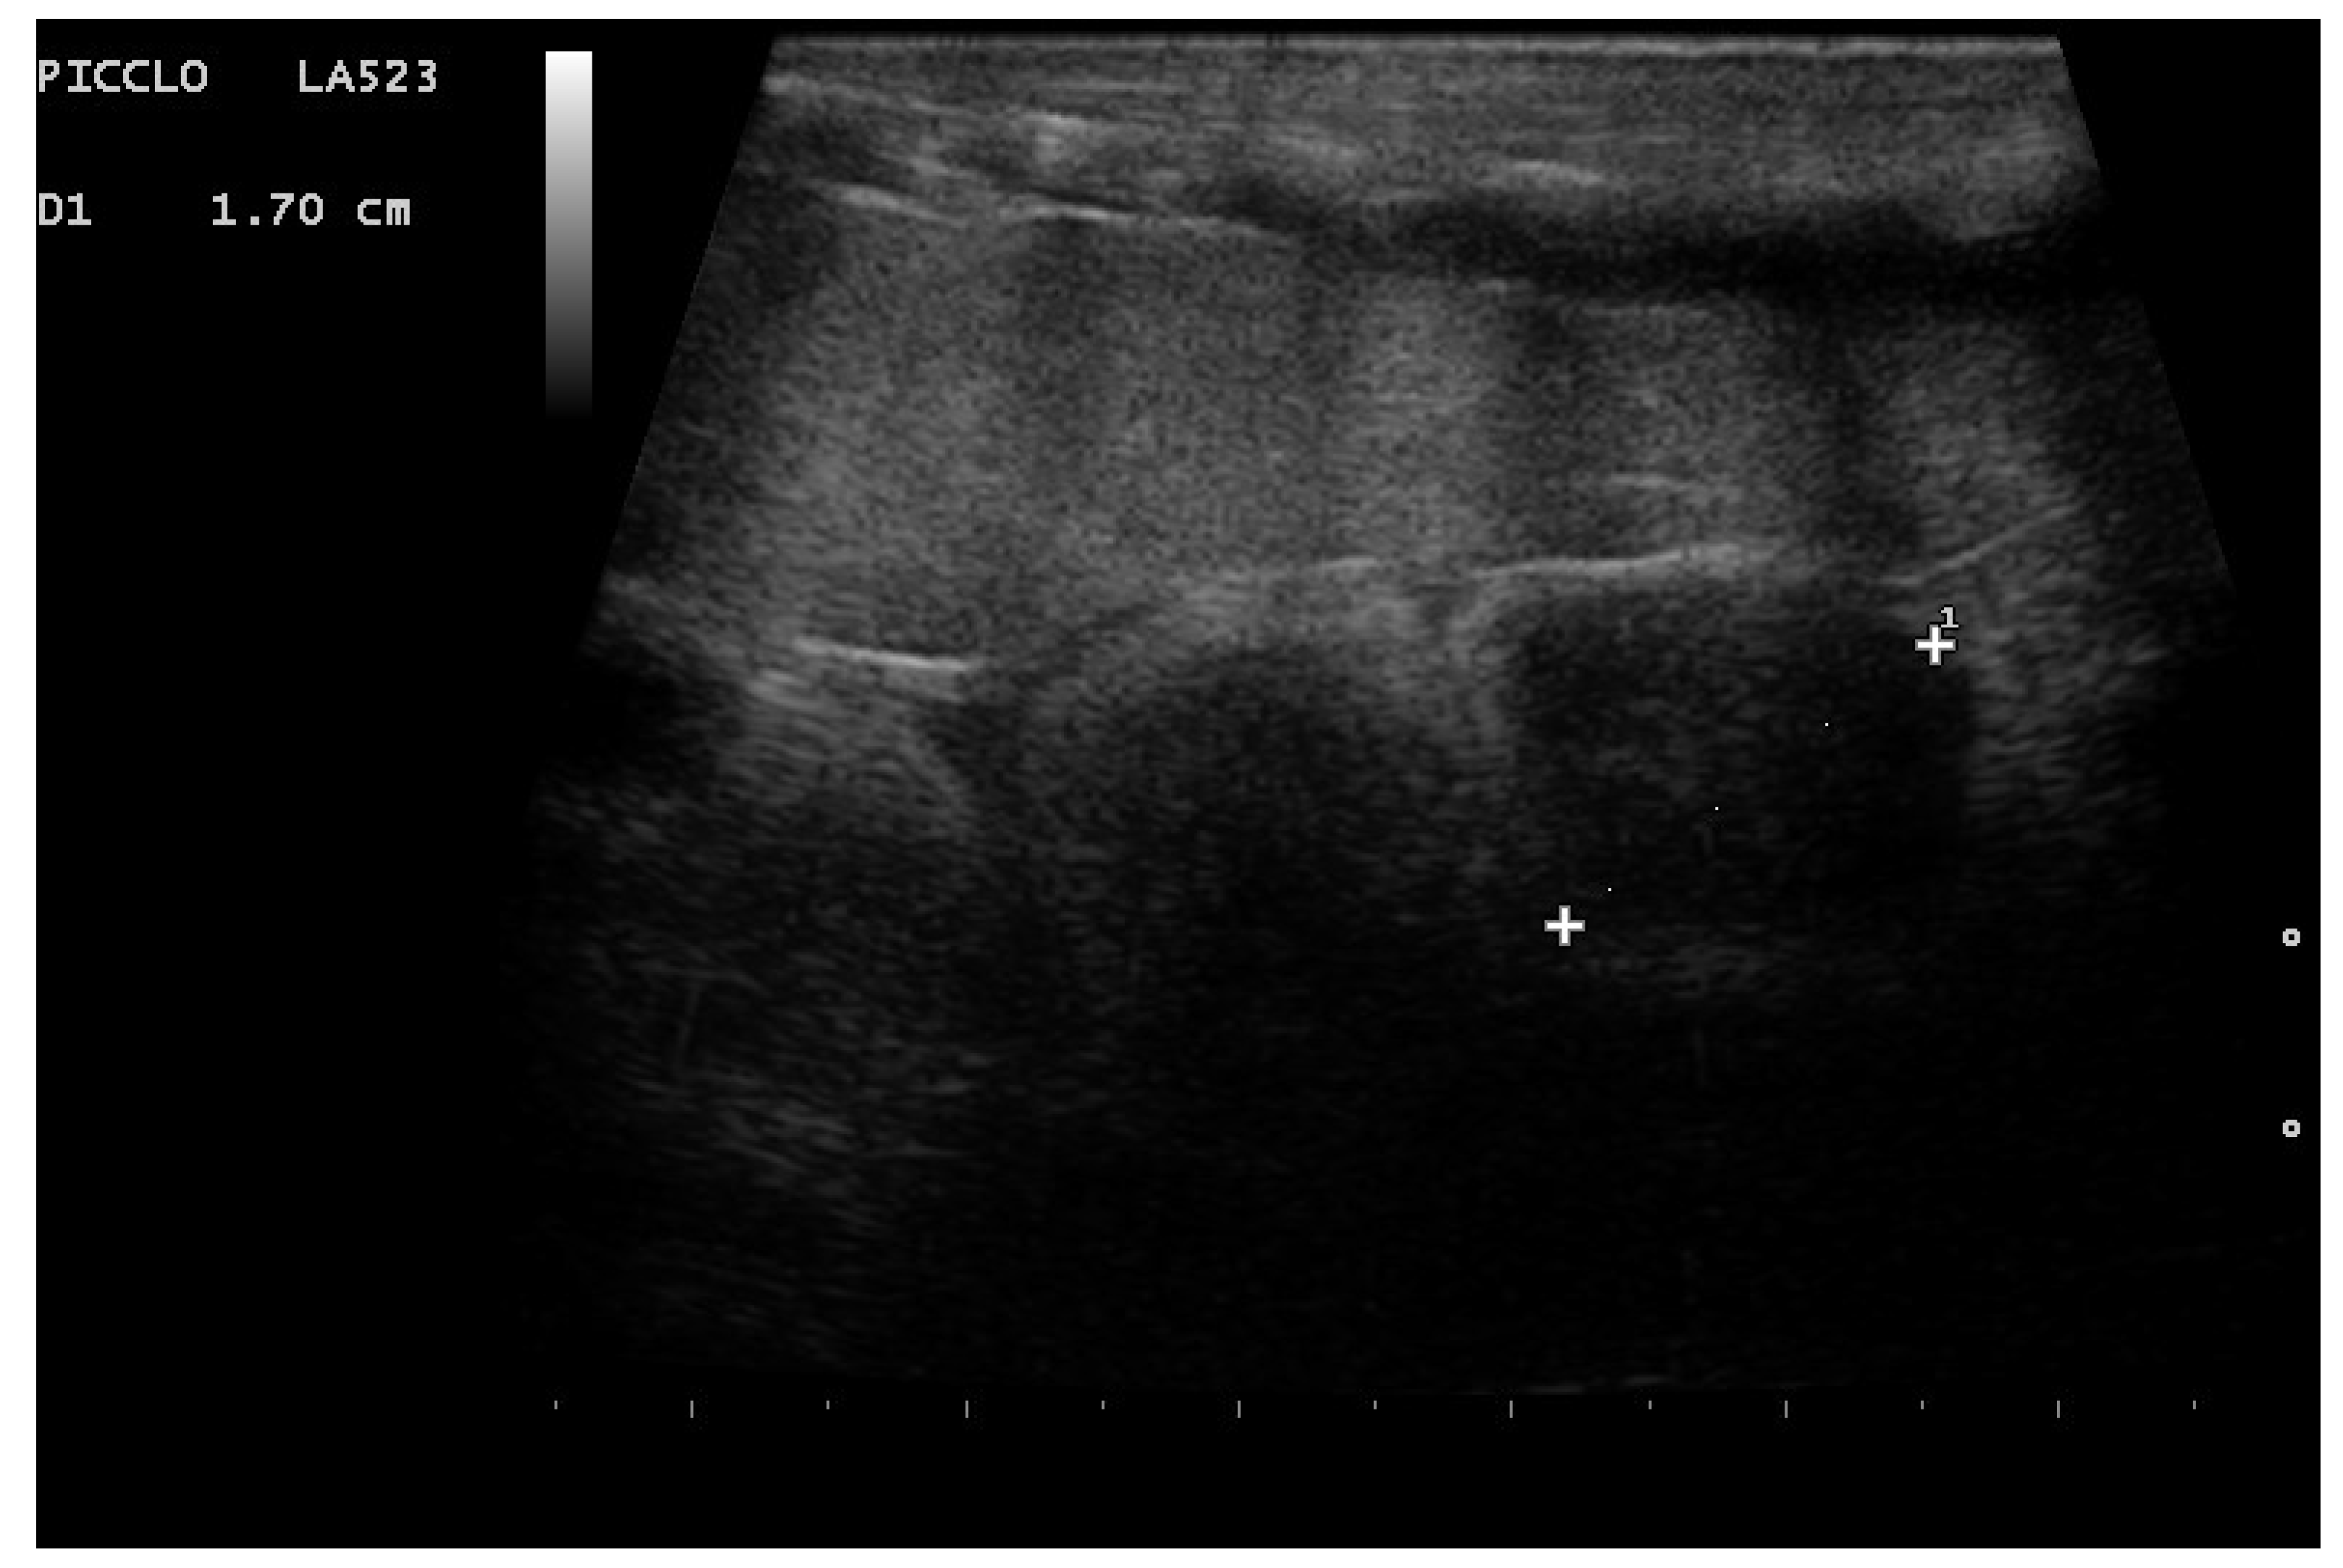

- Garcia, V.C.; Almeida-Santos, S.M. Reproductive cycles of neotropical boid snakes evaluated by ultrasound. Zoo Biol. 2021, 1–10. [Google Scholar] [CrossRef]

- Isaza, R.; Ackerman, N.; Jacobson, E.R. Ultrasound imaging of the coelomic structures in the Boa constrictor (Boa constrictor). Vet. Radiol. Ultrasound 1993, 34, 445–450. [Google Scholar] [CrossRef]